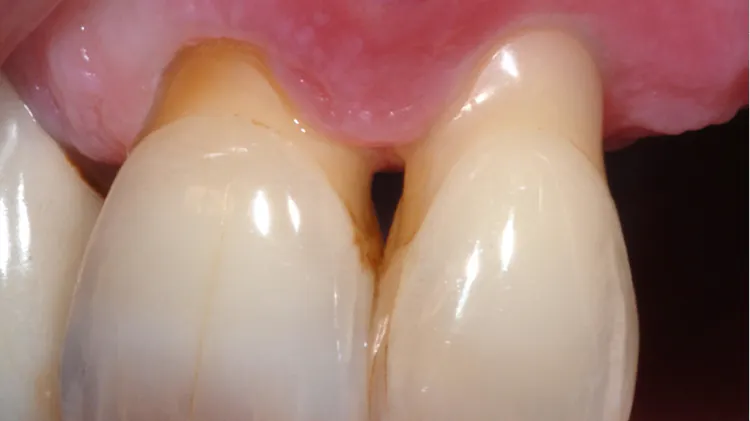

もし一つでも当てはまれば。歯周病かもしれません。 初期歯周病の症状 ・歯を磨いていると歯茎から血が出る ・歯茎がピンクではなく赤くなって腫れている ・歯茎が痛い、むずがゆい ・冷たいものや熱いものを食べると歯や歯茎がしみる 中度歯周病の症状歯周病の初期症状 歯周病はある程度進行してこないとはっきりとした症状が出ない病気です。 そのため、初期段階で気づいて治療を開始できる人は少なく、放置して進行させてしまう人が多いのが現状です。 歯周病の初期症状として以下のようなものが歯周病の初期症状 歯周病は初期の段階に治療することが大切なことをお伝えしました。 次に、初期の歯周病はどんな症状なのかご紹介します。 歯周病の初期段階のことを歯肉炎と呼びます。 歯肉炎とは、歯ぐき(歯肉)に炎症が起こった周病の初期段階です。

歯肉炎 ( 歯周病 )は、歯槽骨(歯を支える骨)や歯茎に炎症、出血などの症状が起こる病気です。 歯周病の初期症状はこれ! チェックリスト 歯周病は、日本人のなかでも7~8割がかかっているといわれている病気です。 歯周病菌が歯を支えている歯周組織に感染し、炎症を起こさせることでそれを支える組織を破壊し、最終的に歯が抜け落ちてしまいます。